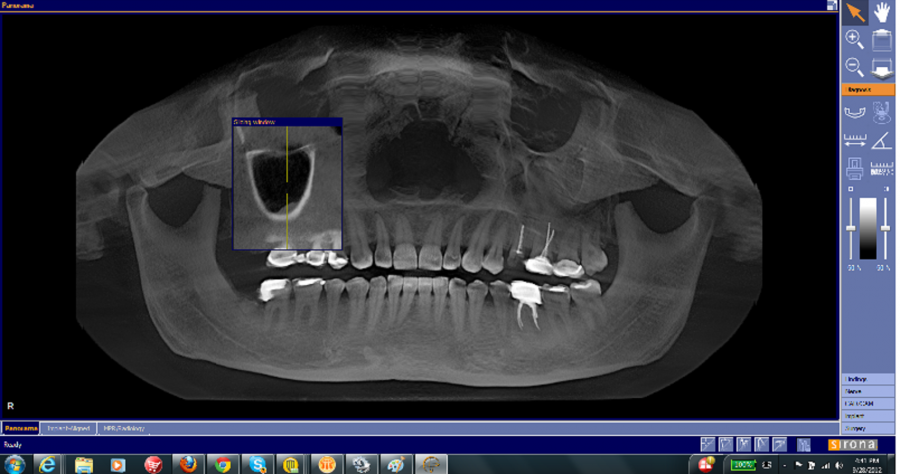

Can you get MRI if you have dental implants?

Can MRI be done with metal implants?

Can you have an MRI with titanium implants?